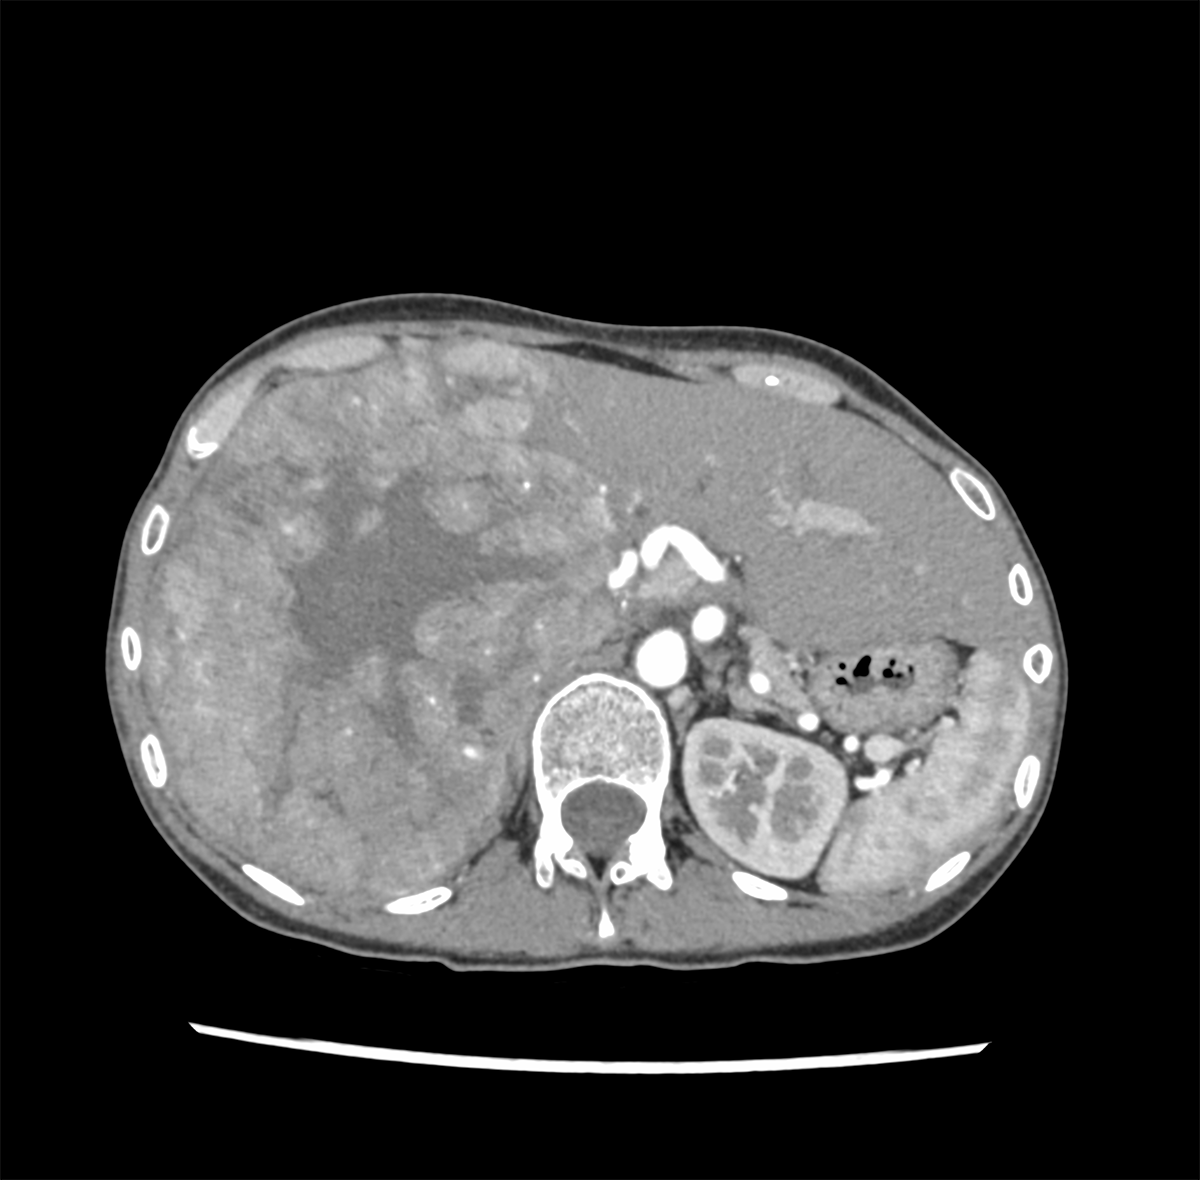

30歳代、女性、38kg、肝細胞癌

右上腹部違和感にて他院を受診し,CTで肝右葉を首座とする巨大肝腫瘍を認め,精査目的に当院紹介.

肝右葉を首座とする24cm大の多結節癒合状の腫瘤性病変を認める.単純CTでは肝実質と等吸収を示し,内部に低吸収域や石灰化を伴っている.造影後早期動脈相から後期動脈相にかけて結節間でやや不均一な早期造影効果を認め,肝静脈相以降では肝実質より相対的に低吸収を示す.門脈本幹から一次分枝レベルにて明らかな造影欠損を認めない.肝細胞癌が疑われ外科的切除が施行され,高~中分化型肝細胞癌と診断された.

肝腫瘍に対する造影CT検査は,画像診断のみならず,外科手術のための血管構築も役割に含まれる.肝動脈,門脈,肝静脈と腫瘍の関係性が重要であり,多時相での撮影をすることで,本症例のように血管の3D画像の作成が可能である.